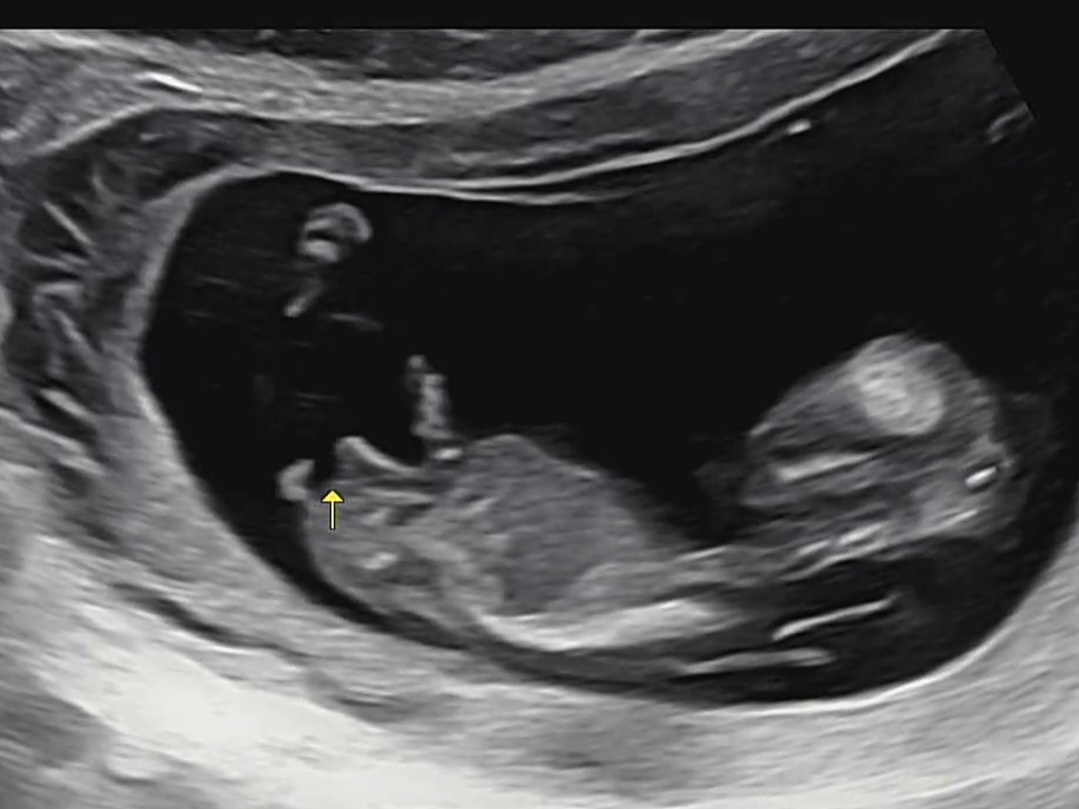

ai는 딸이라고 예측하는데 어떻게 보이세요?

아들 같은데요..?! 각도가 위로 가있으면 아들이라고 했던거 같아요!